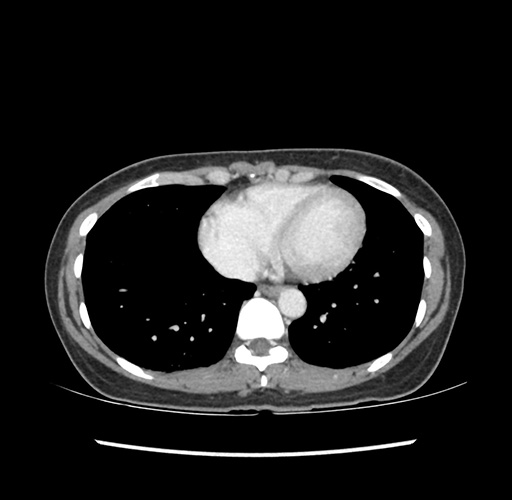

Imaging Analysis

Look through the patient's CT scan to identify any areas of concern for the necessary procedure.

Based on your CT findings, which issue(s) would give reason for "planned slowing down moment(s)" in this case?